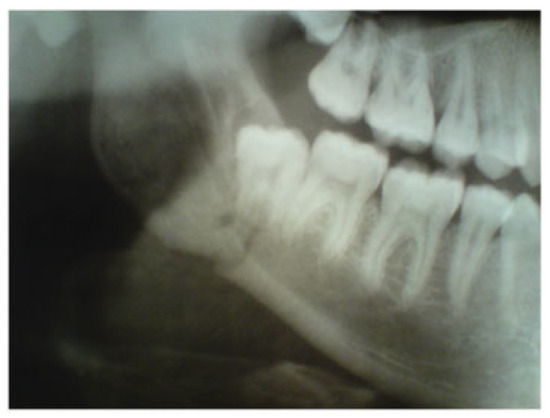

A 23-year-old patient was admitted to the Department of Oral and Maxillofacial Surgery at Lviv National Medical University with complaints of swelling of the cheek, intraoral bleeding, and “bad” bite associated with falling from a bicycle. After complete clinical and roentgenological examination, a diagnosis of traumatic fracture in the right mandibular angle area with fragment displacement and impaction of tooth no. 48 in the fracture line was established (Figure 6). He underwent removal of tooth no. 48 from the fracture line, open reduction, and internal fixation of the mandible with two HMWPE miniplates via combined intraoral and transbuccal approaches (Figure 7). A control X-ray obtained the day after osteosynthesis revealed perfect anatomical reduction and fixation of bone fragments (Figure 8). Temporary MMF was maintained for 3 days after osteosynthesis. The postoperative recovery was uneventful, and good mouth opening was achieved. The duration of the patient’s hospitalization was 8 days.

Figure 8. Fragment of orthopantomogram in a 23-year-old patient. One day after osteosynthesis. Anatomical reduction and fixation of mandibular angle fracture with two high-molecular-weight polyethylene miniplates.